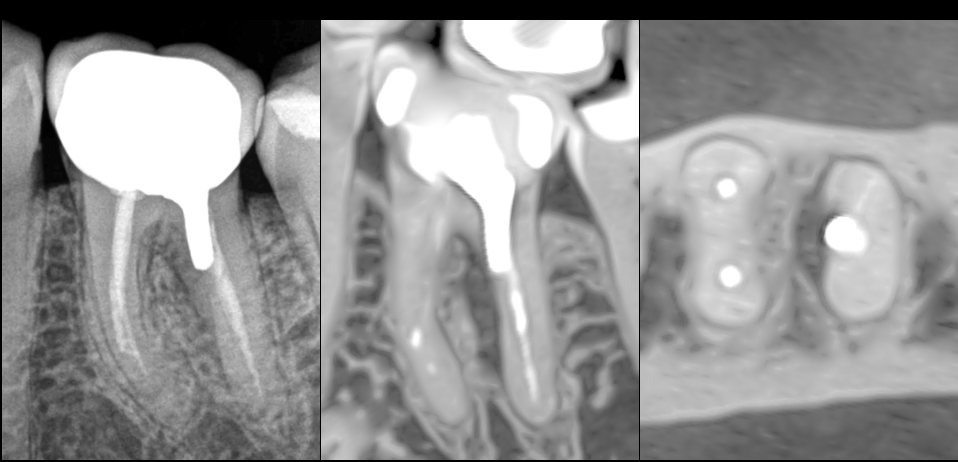

🔍 Pulpe précédemment traitée, os péri apical normal

❓ Mais douleur à la percussion : pourquoi ?

➡️ En raison d’une atteinte de furcation, liée à une perforation lors de la mise en place de l’ancrage corono-radiculaire dans la racine D.

🤔 Peut-on sauver cette dent ?